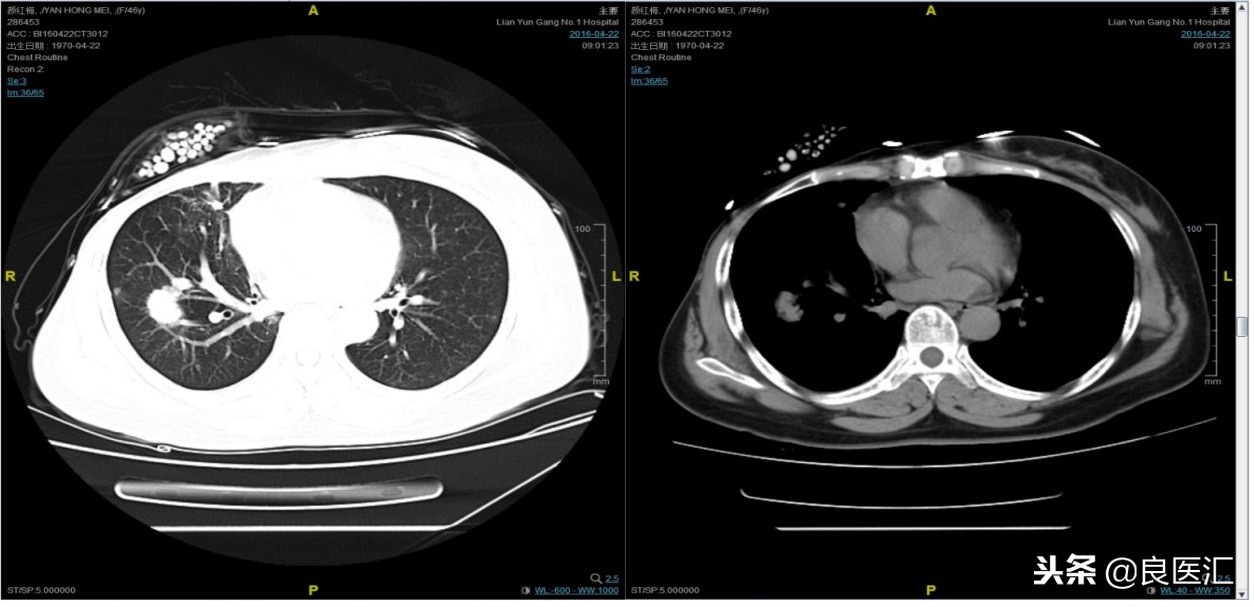

从2016-2-19开始给予紫杉醇+曲妥珠单抗治疗,紫杉醇240mg,3周重复,曲妥珠单抗330mg三周重复。患者末次应用曲妥珠单抗和紫杉醇时间为2016-6-24,紫杉醇共应用4周期。

期间2016-4-22复查CT如下: